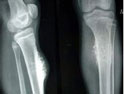

軟骨肉瘤是常見的惡性骨腫瘤之一,發(fā)生于髓腔者為中心型,發(fā)生于骨膜者為骨膜型,另有少數(shù)可發(fā)生于軟組織。腫瘤好發(fā)于四肢長(zhǎng)骨與骨盆,也可見于椎骨、骶骨、鎖骨、肩胛骨和足骨。本病分原發(fā)和繼發(fā)兩種,后者可由軟骨瘤、骨軟骨瘤惡變而來,這也是發(fā)病年齡較晚的原因之一。本病多見于成人,30歲以下少見,35歲以后發(fā)病率逐漸增高。男性多于女性。